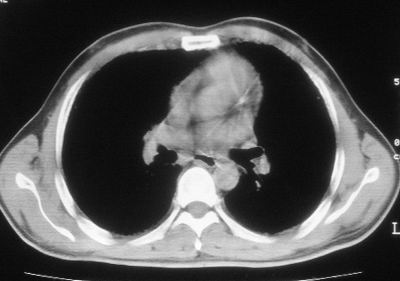

患者,男,44岁,糖尿病4年余,近期消瘦、乏力。化验检查:总胆红素26.33(参考值:5.1-17.2u mol/l),直接胆红素:6.4(参考值:0-4.3u mol/l),谷-丙转氨酶(alt):843(参考值:<40u/l),hbsag(+),抗hbs(-),hbeag(-),抗-hbe(+),抗-hbc(+)。

1\\粟粒性肺结核可能性大,支气管肺泡癌不排除

双肺散在小结节影,考虑粟粒性肺结核.肺窗薄扫会更好看些.

双肺外侧带胸膜下可见网状阴影,考虑轻度肺间质纤维化。

诊断:癌性淋巴管炎.

双肺纹理增强并可见网格状影达外带,考虑双肺感染并轻度间质纤维化

1.双肺急性粟粒型肺结核;2.少量腹水.

肺间质纤维化并肺部感染,结合不能排出,毕竟糖尿病人易合并之,建议结合ppd检查或hrct进一步扫描。